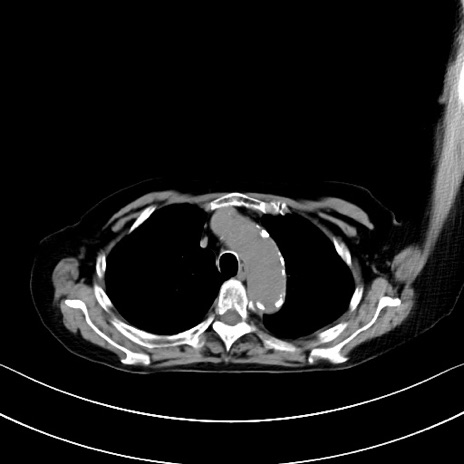

横断像